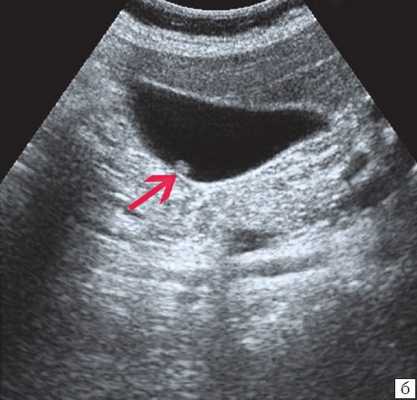

Ультрасонография является эффективным средством выявления полиповидной формы холестероза 9. Традиционной считается следующая сонографическая характеристика холестериновых полипов: неподвижные гиперэхогенные структуры, которые не дают акустической тени и прикрепляются к стенке желчного пузыря. Контуры таких образований, как правило, ровные, а размеры таких образований различны, чаще не превышают 10 мм (рис. 2).

![УЗ-картина полипов в желчном пузыре - полиповидно-сетчатая форма холестероза (2в)]()

в) Полиповидно-сетчатая форма холестероза, полипы размерами до 5 мм, повышенной эхогенности.

Однако, по некоторым данным, размеры холестериновых полипов могут быть более 20 мм. Кроме того, полипы больших размеров (в 7% от общего числа) могут иметь пониженную эхогенность и фестончатый контур.

Мелкие холестериновые включения, образующие диффузную сеточку в толще подслизистого слоя размерами 1-2 мм, выглядят как локальное утолщение или уплотнение стенки желчного пузыря и в некоторых случаях (см. рис. 2) вызывают реверберацию (эхографический симптом "хвост кометы").